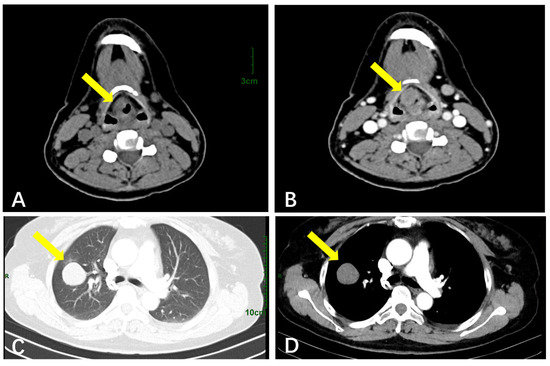

| Soft Tissue | Ultrasound (n = 26) | Well-circumscribed hypoechoic masses (n = 25, 96.1%); sparse blood flow. | Larger size (mean: 93 mm); rare irregular margins. |

| CT (n = 9) | Well-defined hypodense nodules (n = 9, 100%); moderate enhancement | N/A | |

| Respiratory System | CT (n = 5) | Round/oval hypodense masses; lobulated contours; mild–moderate enhancement | A larger size (mean: 50 mm); no pathognomonic signs. |